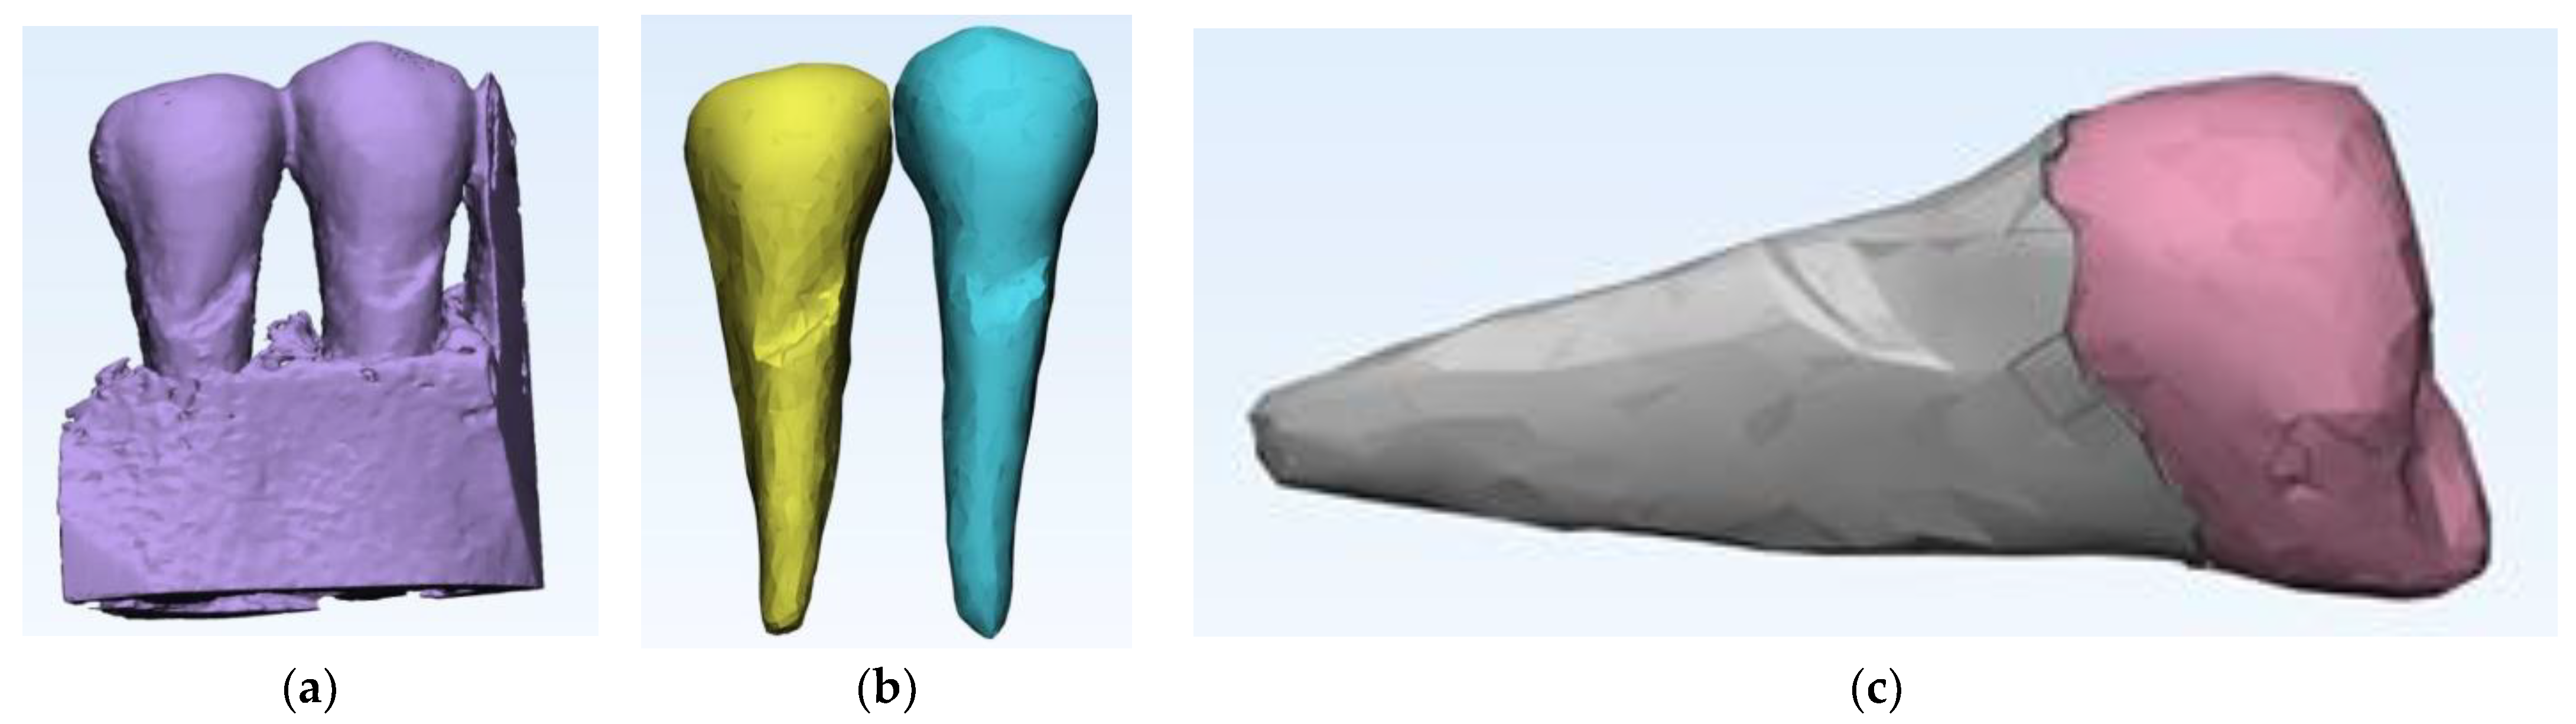

2. Case Description

3. Finite Element Analysis (FEA) of Mandibular Right Premolars